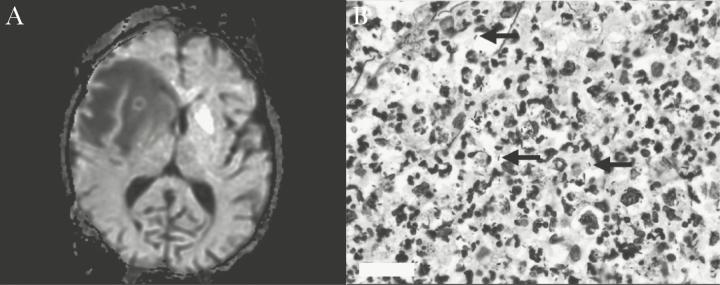

Diagnosis of Extrapulmonary Legionellosis in Allogeneic Hematopoietic Cell Transplant Recipients by Direct 16S Ribosomal Ribonucleic Acid Sequencing and Matrix-Assisted Laser Desorption/Ionization Time-of-Flight Mass Spectrometry.

Identifying extrapulmonary legionellosis is difficult due to the lack of clinical suspicion and limitations of conventional microbiologic methods. We present a case series of hematopoietic cell transplant recipients with extrapulmonary legionellosis diagnosed via molecular diagnostics: 16S ribosomal ribonucleic acid gene Sanger sequencing and matrix-assisted laser desorption/ionization time-of-flight mass spectrometry.